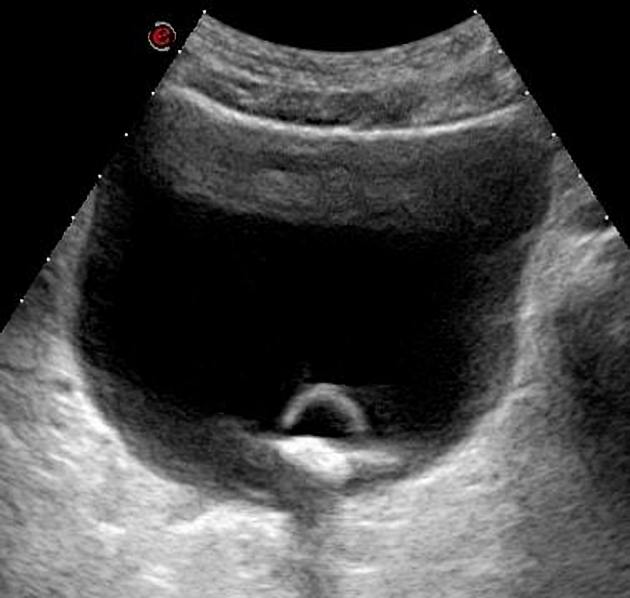

Para los hombres que desarrollaron cáncer de próstata, se obtuvieron registros médicos para determinar la edad al momento del diagnóstico, el nivel de antígeno prostático específico y el estadio y grado del tumor.

Durante el seguimiento se diagnosticaron 3.839 casos de cáncer de próstata. Una de las observaciones principales fue que la frecuencia de la eyaculación por mes disminuyó con la edad.